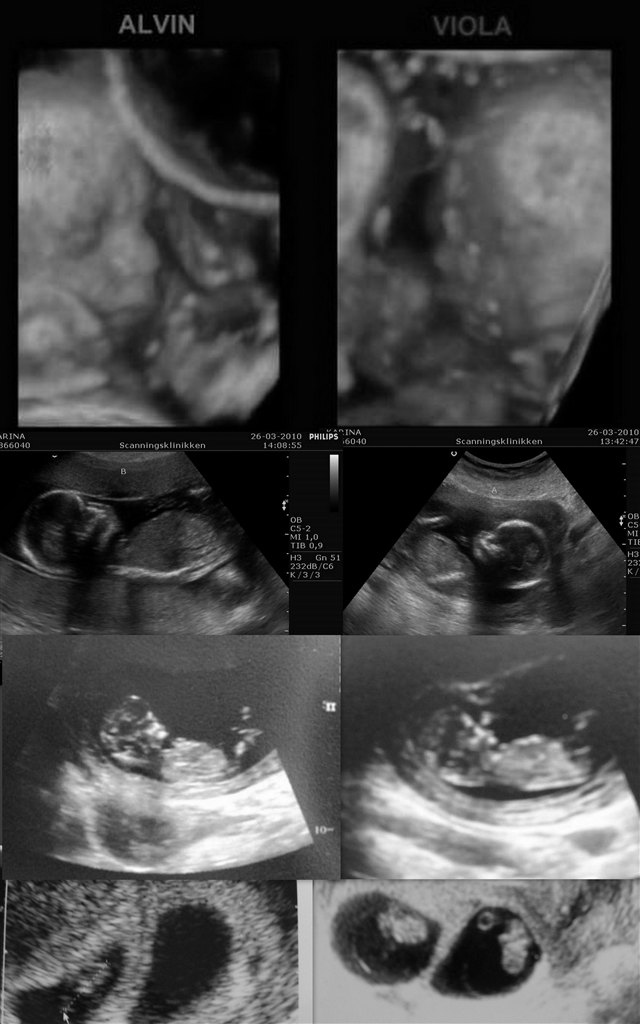

dejlige billeder... hvor langt er du henne på det nedereste til venstre ??

7+0 og man kan næsten ikke se den ene i sin sæk. Der var hjerteblink i begge. Lægen sagde, at han aldrig ville se efter hjerteblink før 7+0, da det bestemt ikke betød, at der ikke var liv, hvis man ikke kunne finde det.

Til højre er jeg 9+0. Der blev de til små "vingumibamser".